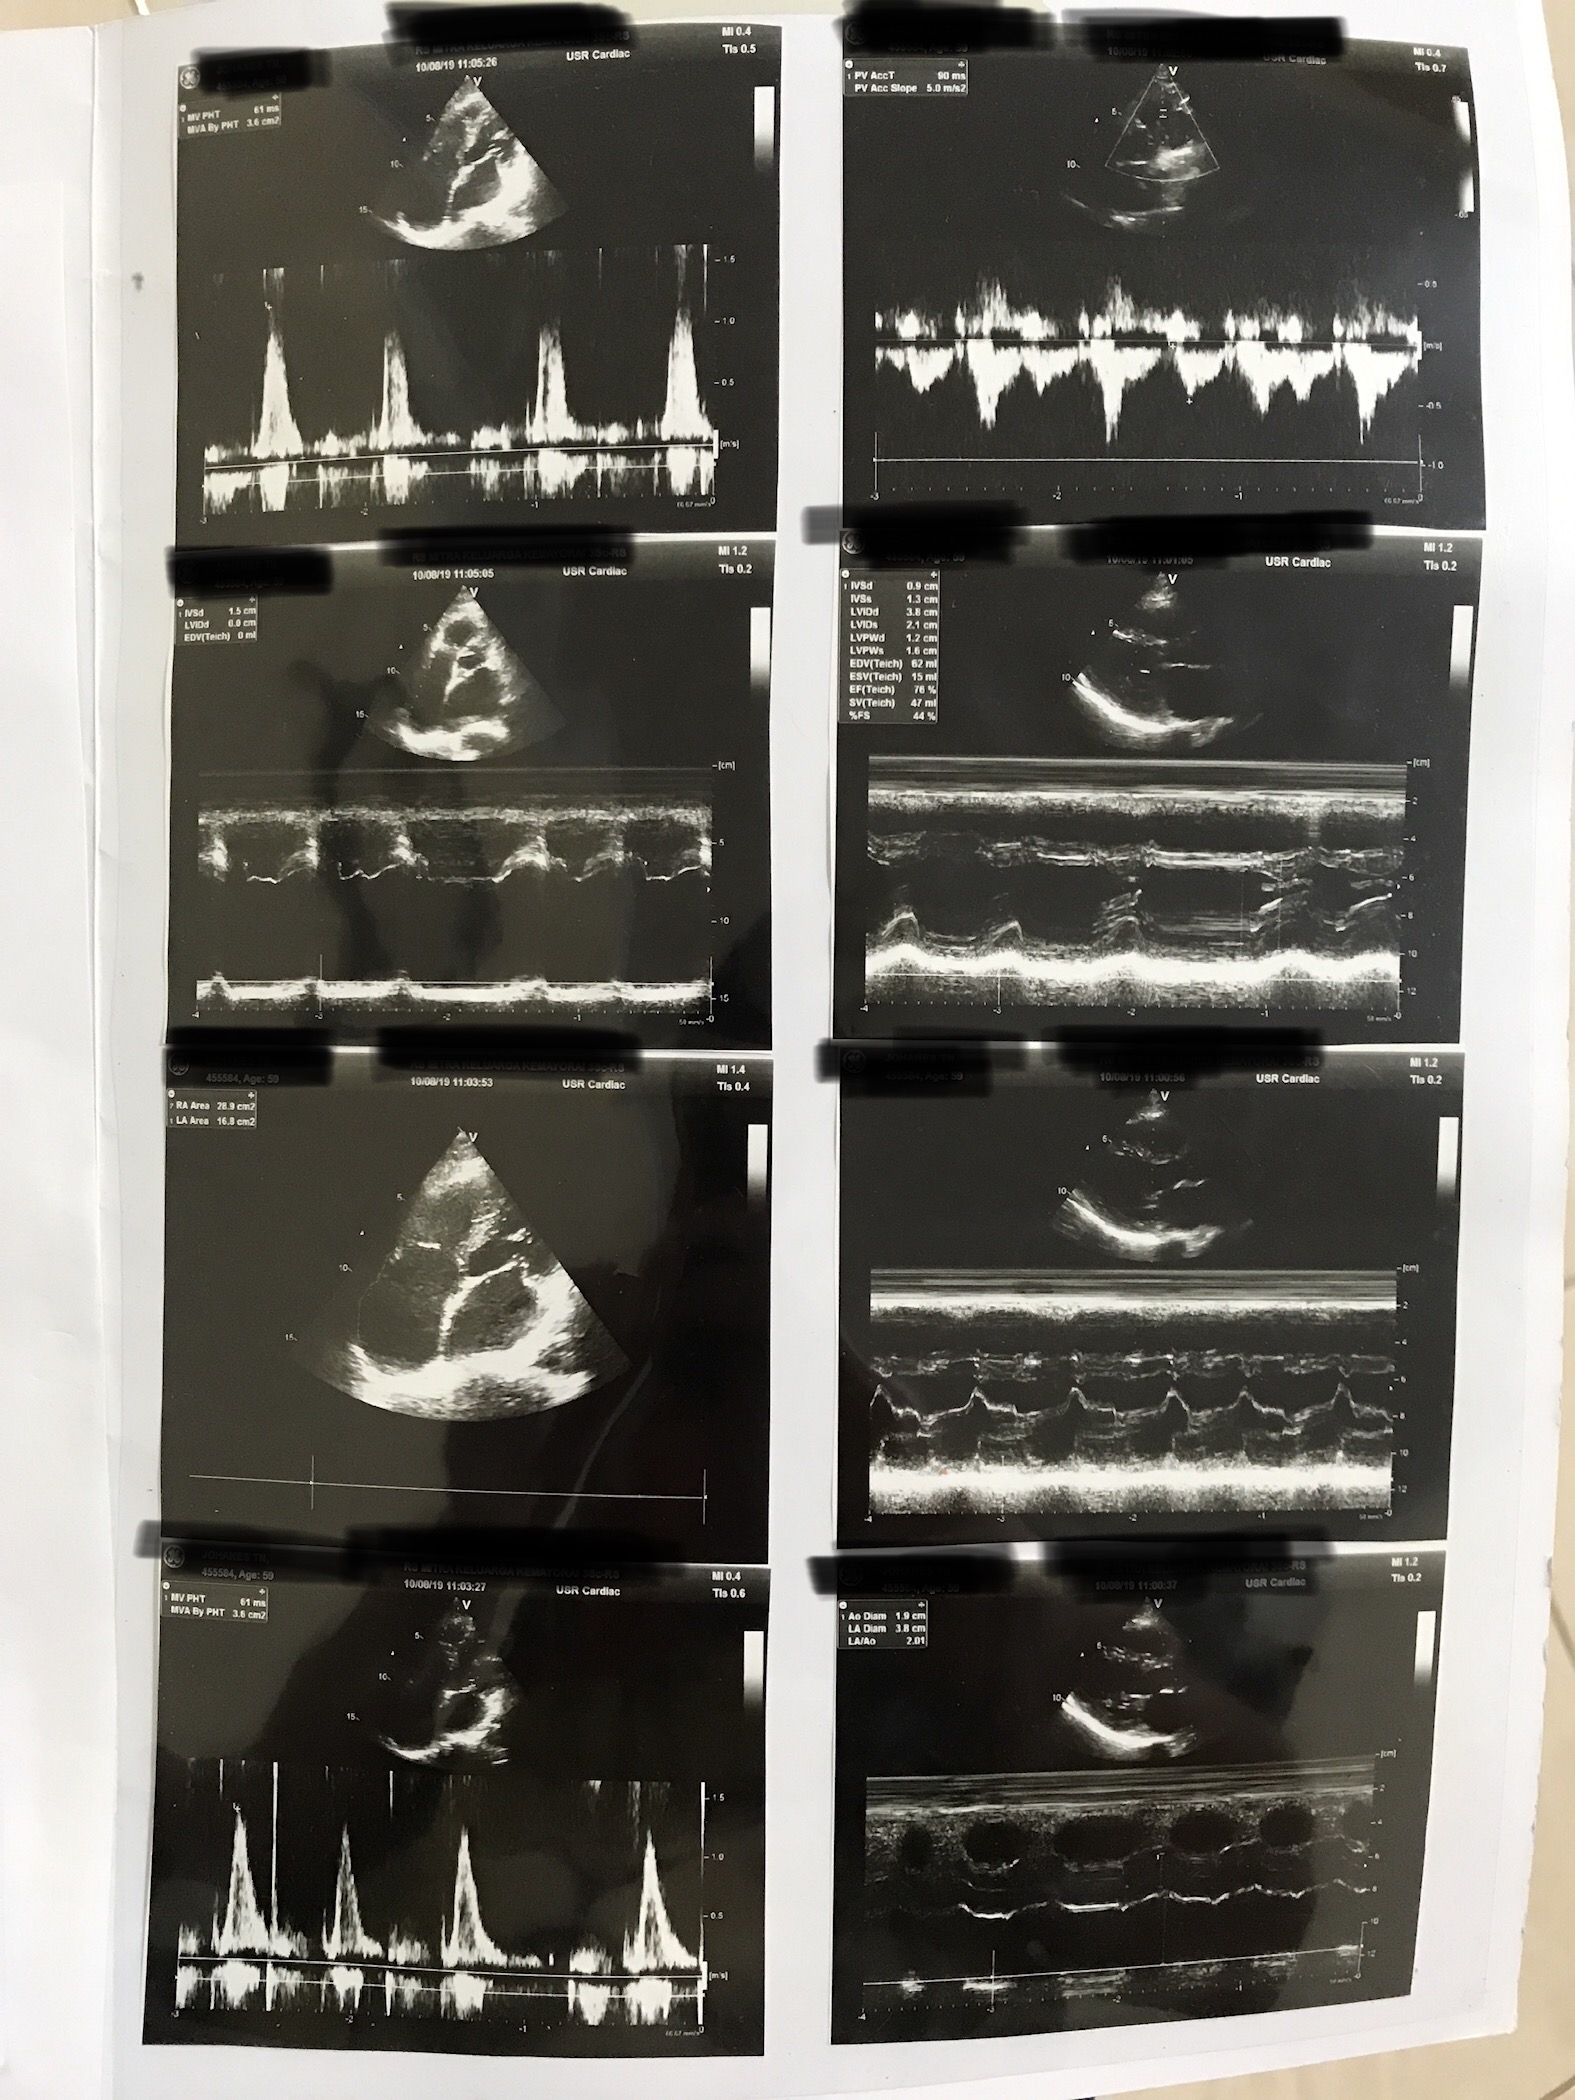

My dad is diagnosed with arryhthmia (which he already have for 30 years, the doctor write AF on his medical report) with Mild mitral insufficiency and moderate tricuspid insufficiency (7 years ago he did an echo and there was no problem with his valve) Here are some conditions my dad have -My dad doesnt have breathlessness for daily activities. -My dad always cough after he drinks and very often have frothy white saliva (any explanation?) - he very often feel bloating esp at night - his cholesterol level sometimes high. Here are his echo report RV function decreased TAPSE 15mm. E/A < 1 diastolic relaxation dysfunction. LVEF 76%. diastolic dysfunction gr. 1. RA is not dilated. MI mild and TI moderate. How’s the prognosis? And life expectancy? Do most people live a long and good life with this condition? Does surgery is needed for sure?? Is antiplatelet needed for my dad?? Cause the cardiologist didnt give my dad medicine at all